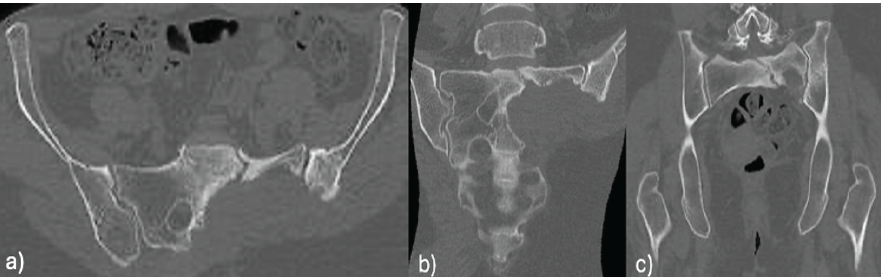

Six months post-operatively, the patient presented with progressive lumbosacral pain and gait impairment. The CT scan identified an insufficiency fracture in the vertebral body of S1 and the remnant of the left sacral ala (Fig. 4), without evident tumor recurrence or associated fluid collections.

Figure 4: 6-month post-operative pelvic computed tomography scan: Insufficiency fracture on the left sacral ala.